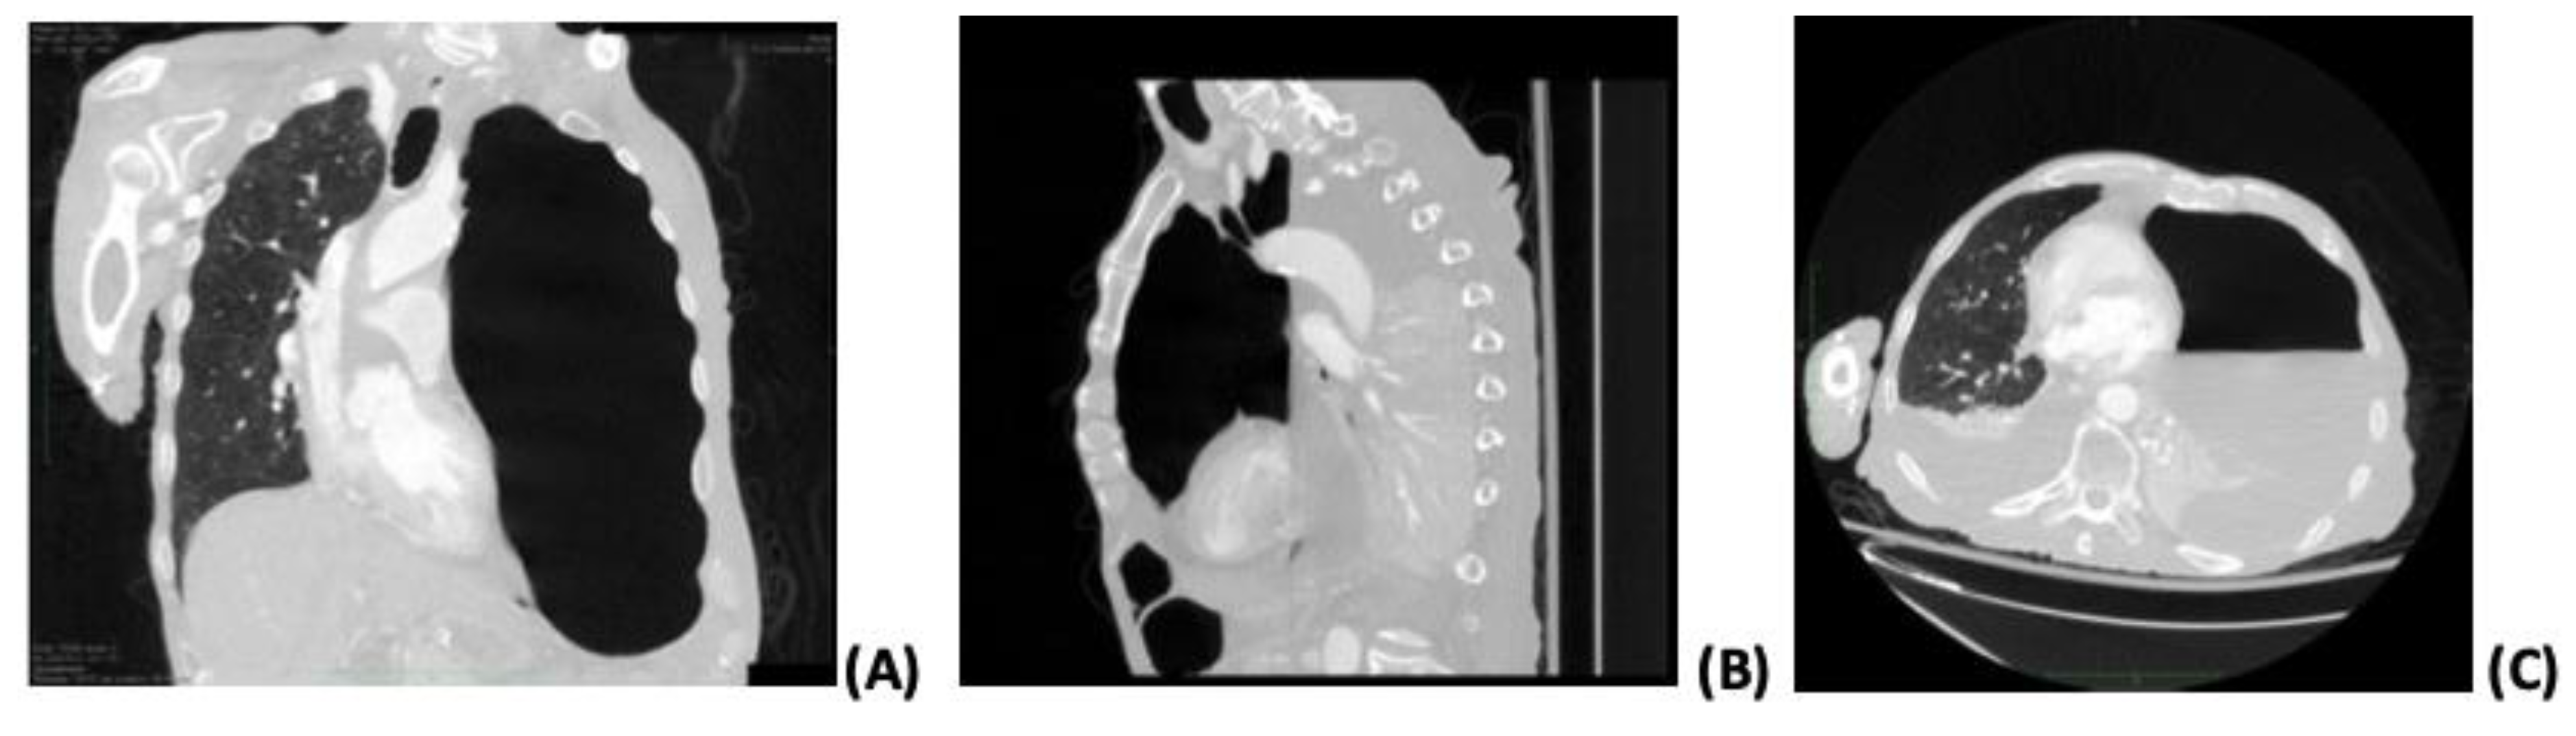

On the sixth day of hospitalization, the patient deteriorated clinically, with a high fever and elevation of inflammation markers on laboratory exams. Blood, urine, and sputum cultures were obtained, with negative results. In addition, antimicrobial treatment was upgraded to piperacillin-tazobactam and linezolid on the same day. A chest X-ray was performed, which showed consolidation in the upper left pulmonary lobe with a gas-fluid level. On the eighth hospital day, a thoracic CT scan confirmed an almost complete left lung collapse due to hydropneumothorax with features suggestive of necrotizing pneumonia and a right mediastinal shift. Figure 1 shows the findings of the CT. A chest tube was inserted into the left hemithorax, draining a semi-clear, yellow fluid and air. Diagnostic pleural analysis revealed an exudate effusion with 9.600 cells/μL leukocytes (87% neutrophils), while Gram stain detected Gram-negative bacilli. Table 2 shows the pleural fluid analysis. On the 16th hospital day, the pleural fluid culture revealed the growth of a MDR K. pneumoniae and P. aeruginosa. Thus, a diagnosis of necrotizing pneumonia complicated by hydropneumothorax was made. Empirical antimicrobial treatment was modified according to the antibiogram, with a combination of piperacillin-tazobactam and levofloxacin to increase the coverage on P. aeruginosa. This antimicrobial regimen was administered for 12 days in total.

Figure 1.

Computed tomography findings. Coronal (A), sagittal (B), and axial (C) planes show severe volume left-sided hydropneumothorax accompanied by distinct areas of low attenuation with decreased parenchymal enhancement of the upper left lobe, indicating necrotizing pneumonia.